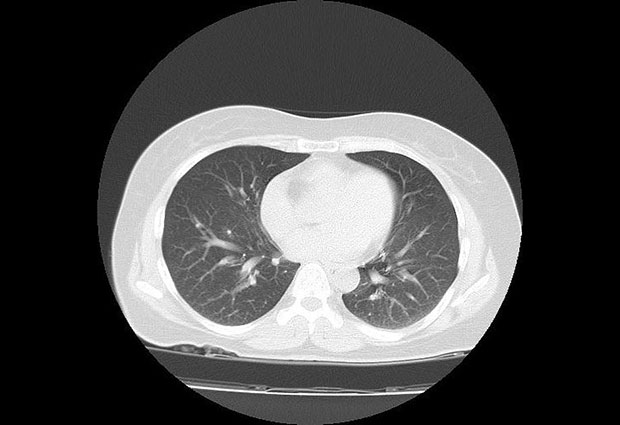

Lekarska zajednica bruji o slučaju 30-godišnjakinje iz Australije koja je, nakon što joj se rođak zarazio i preminuo usled infekcije korona virusom, insistirala da joj se uradi snimak pluća iako nije imala nikakav simptom zaraženosti.

Lekae je nakon njenog upornog insistiranja pristao da joj uradi snimak iako, naglašava, osoba bez simptoma inače ne bi bila tako detaljno pregledala. A onda, nakon što je snimak urađen, usledilo je iznenađenje - delovi pluća nalikovali su zamagljenom staklu. To je bila tečnost i ukazivalo je na to da je mlada žena zaista zaražena korona virusom. U naredna dva dana, test je to i potvrdio, a ona je hospitalizovana.

Sliku njenih pluća objavila je Radiopedija, a snimak je objavio iranski radiolog dr Barham Rasuli.

Snimak se sada deli među lekarskom zajednicom širom sveta.

- Veoma je važno da ovo vide radiolozi, ali i svi medicinski radnici širom sveta. Mnogo je asimptomatskih slučajeva zaraženosti, a kod nekih od njih odvijaju se ovako ozbiljni i teški upalni procesi - upozorava Endrju Dikson, radiolog iz bolnice Alfred u Melburnu.